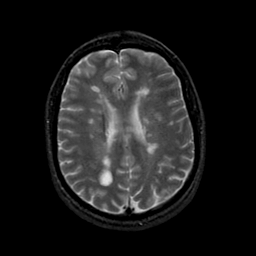

MR Study #23, January 26, 1992 -- Slice #32